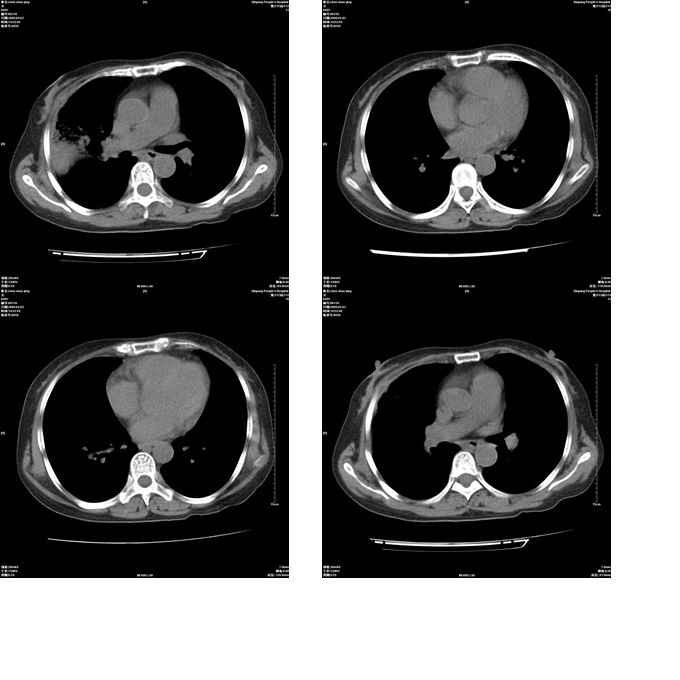

患者,女,48岁,发热伴陈发性咳嗽5天,偶尔痰中带血。体温约38°~40°;白细胞明显减低0.85x10的9次方/升。入院后抗炎、抗痨一周复查病灶明显进展。

右上肺后段实变影,内见支气管气象,肺门未见软组织肿块,气管前方有肿大淋巴结。左下肺见多个类圆形结节影。考虑:1.右上肺后段大叶性肺炎,需进一步检查病原体种类,应多询问病史,条件许可考虑做纤支镜检查2.左下肺结节影性质待定

考虑右上肺后段大叶性肺炎不除外结核,伴双肺结节播散灶,希定期复查。

问题是抗炎治疗一个星期后病灶进展。

右肺于酪性肺炎并左肺播散。

考虑两肺继发性肺结核(右肺上叶干酪性肺炎?)。

考虑两肺继发性肺结核(右肺上叶干酪性肺炎)。

右肺干酪性肺炎并左肺播散。

右肺片状实变影,左肺结节影,抗炎及抗捞治疗后病灶进展。

我考虑:不能除外肺炎型肺泡癌可能。建议查痰或活检。